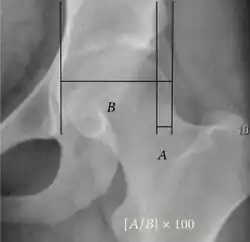

| Acetabular depth ratio |

|

Deepness of acetabulum. | >250